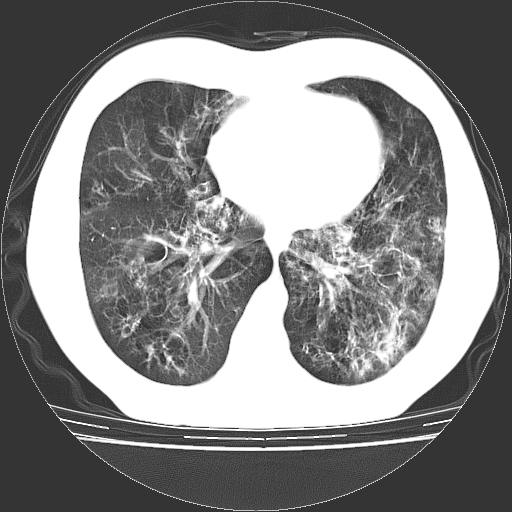

以下是引用zyx168在2006-12-4 15:30:00的发言:[br]经典!支气管肺囊肿并感染。

以下是引用dyqct在2006-12-4 17:11:00的发言:[br]典型的囊状支扩合并感染。

以下是引用liaoqiang在2006-12-4 16:12:00的发言:[br]局部肺叶内可见扩张的支气管壁,考虑为支扩。部份囊样影内有小液平和肺内散布斑片征影、小结节及纤维灶,提示支扩伴感染,且由于局部呈现有树芽征感染以结核可能性大。

以下是引用zhoucan076在2006-12-4 16:48:00的发言:[br]囊状支扩合并感染